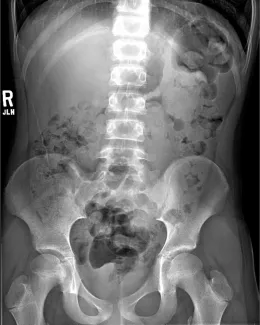

X-ray of clean colon

X-ray of constipated colon

Abdominal Xrays are necessary to evaluate the effectiveness of the laxative or enema therapy and to identify the amount of stool in the colon. These will be done at each office visit.

Also, the surgeon or surgical nurse will determine if there is hard stool by rectal exam. If found, this can be treated by enemas or suppositories, If these fail to help the stool pass, it might be necessary to disimpact the stool in the operating room, under anesthesia.

Firm bowel movements can be painful to pass. This can lead to stool with-holding which further worsens constipation. Blood streaks lining the firm stools may mean anal fissures, which are cracks or tears near the anus caused by passing hard stools. If this is noted, increase fluid intake and call our office to schedule a clinic visit and an abdominal Xray. The dose of oral laxatives may need be increased before the clinic visit.